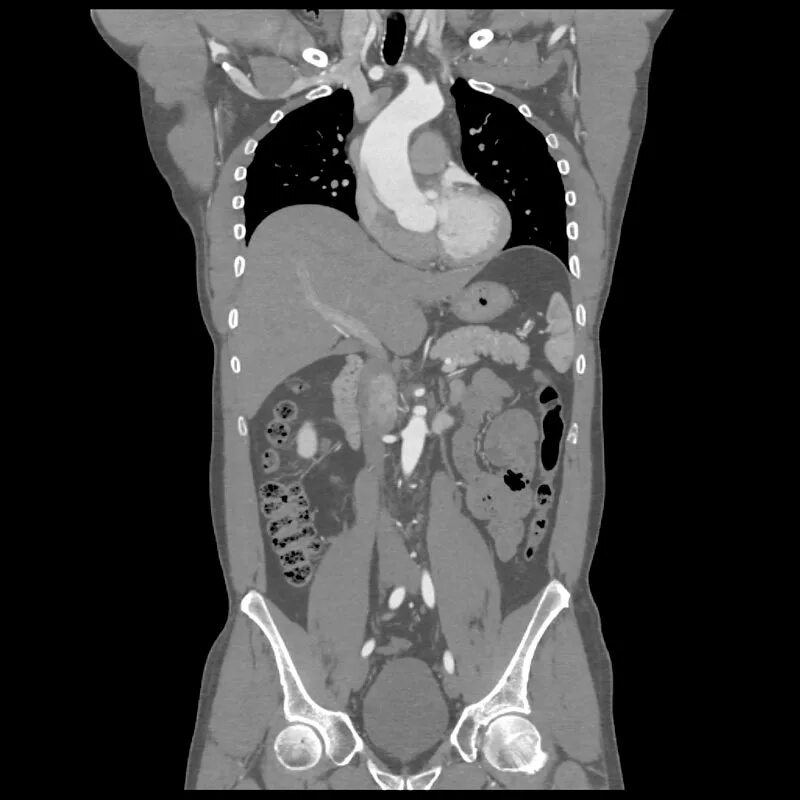

3 обп